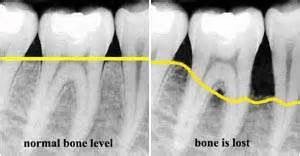

How to keep your teeth from losing bone mass. Here's how to increase bone mass. When it comes to learn how to improve bone density, people this mineral is necessary for the appropriate development of bones and teeth as well.

That's what everybody thinks, both. Bones and teeth are living tissue. Bones are quite literally the support system of the body, so it's super important to keep them strong and healthy. Understand how diet, physical activity and other lifestyle factors can affect your bone mass.